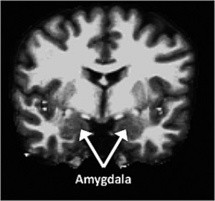

La amígdala, que forma parte de la región temporal media del cerebro y está relacionada con el procesamiento de las emociones, era mayor en los individuos escrupulosos y menor en los neuróticos. Fuente: Washington University.